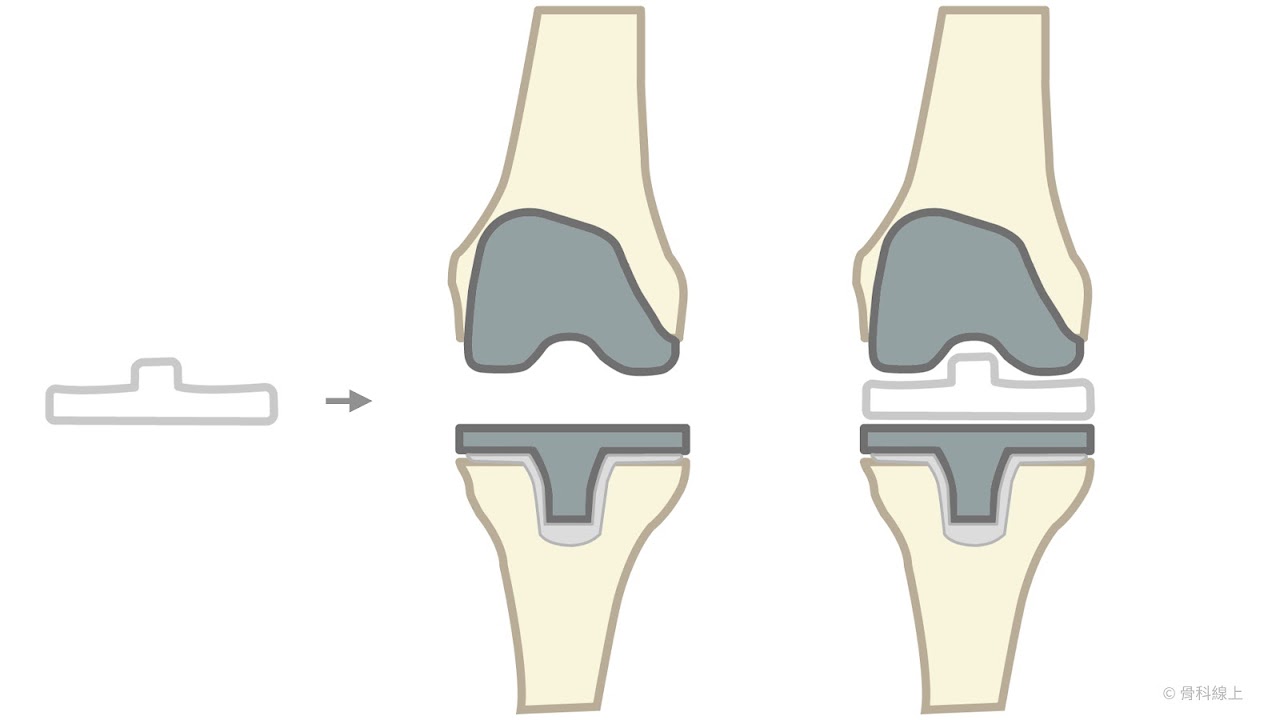

部分人工膝關節置換手術過程示意圖

因為膝關節退化常磨損在內側,半膝關節置換手術的概念,在於處理內側磨損的關節表面,使其光滑(resurfacing),除了內側半月板以及關節軟骨以外的構造基本上都能保留,目標在於『哪裡磨損換哪裡』,預期破壞結構較少,能夠恢復得較快,保留更大部分自己的韌帶軟骨,讓膝蓋活動更自然。